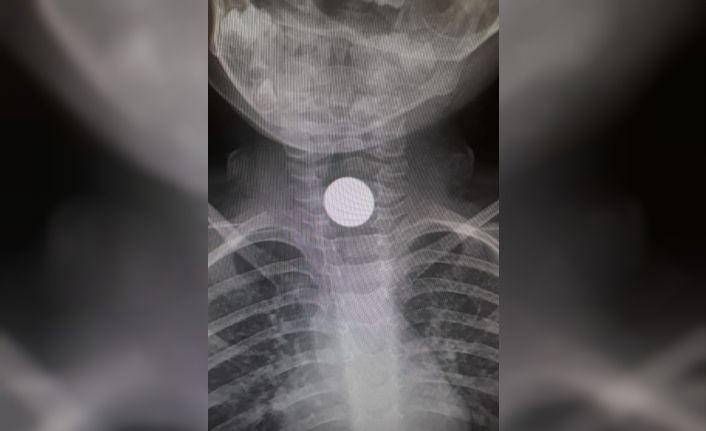

Alınan bilgiye göre göre, 3 yaşındaki Yunus Emre K, evde oyun oynadığı sırada yerde bulduğu parayı ağzına attı. Bozuk para boğazına kaçtı. Aniden fenalaşan çocuk ailesi tarafından hastaneye kaldırıldı. Burada çekilen röntgende küçük çocuğun boğazına metal para kaçtığı anlaşıldı. Yapılan ilk müdahalenin ardından küçük Yunus, boğazında kalan paranın çıkarılması için Bursa’ya sevk edildi. Bursa Şehir hastanesinde yapılan müdahale sonucu paranın çıkarıldığı öğrenildi.